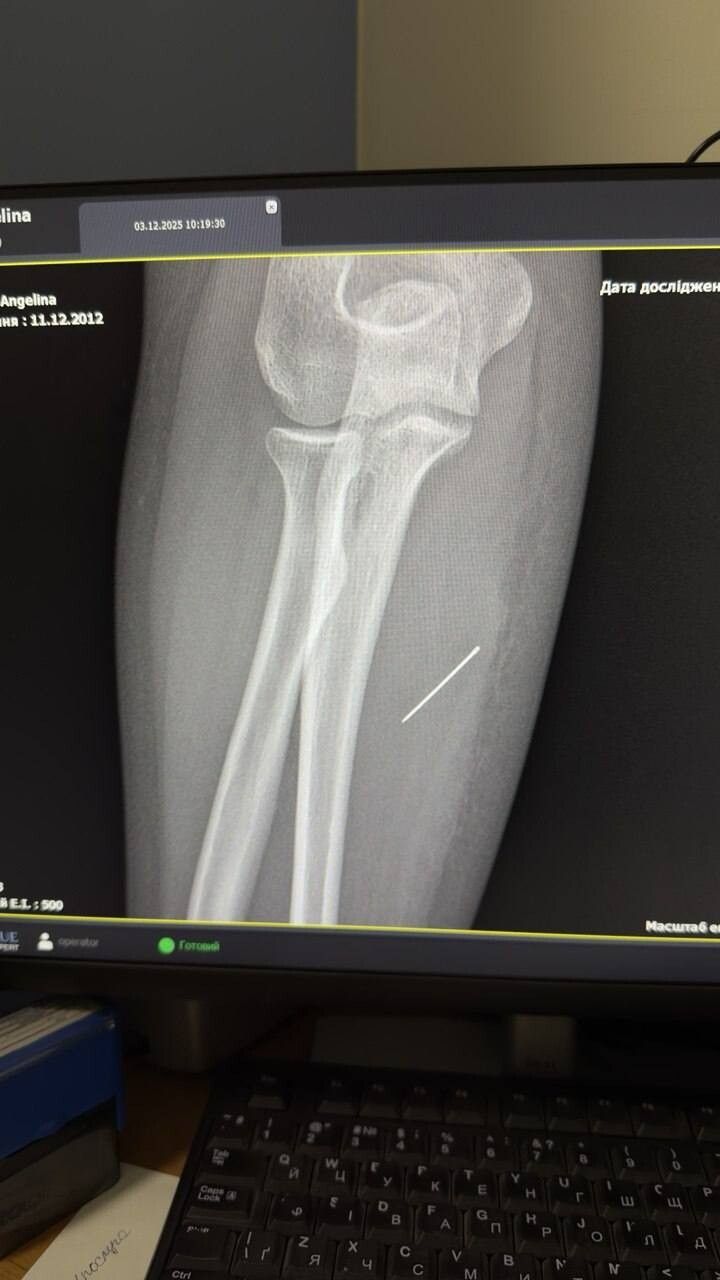

За той тиждень, що Ангеліна проходила з голкою, та просунулася глибше. Вже на рентгені лікарі чітко побачили, що голка зайшла під кутом 45 градусів і застрягла глибоко в товщі м’яза. Якби вона мігрувала ще далі, то могла б пошкодити або судини, або нервові закінчення.

Під час операції критично важливим було витягнути голку точно за траєкторією її входження, щоб вона не зламалася. Адже пошук дрібних уламків у м’язах є значно важчим завданням. За допомогою рентген-навігації ЕОП хірурги точно визначили місце знаходження стороннього тіла, невеликий розріз та правильно і безпечно його вилучили.